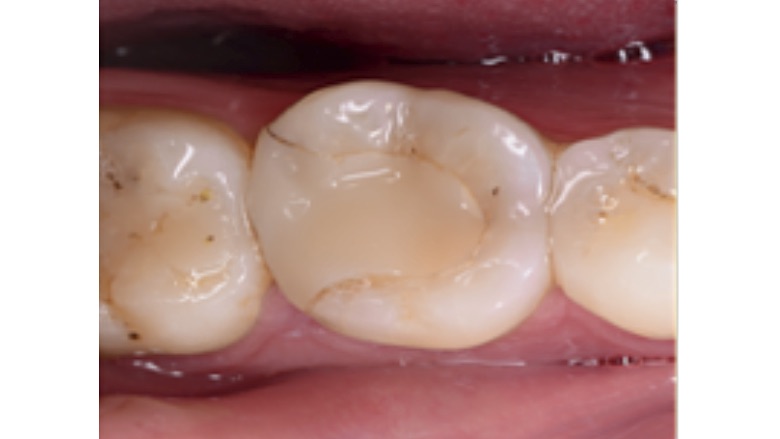

Fig. 7. Radiografía final del retratamiento no quirúrgico del 3.6. con su restauración indirecta cementada.